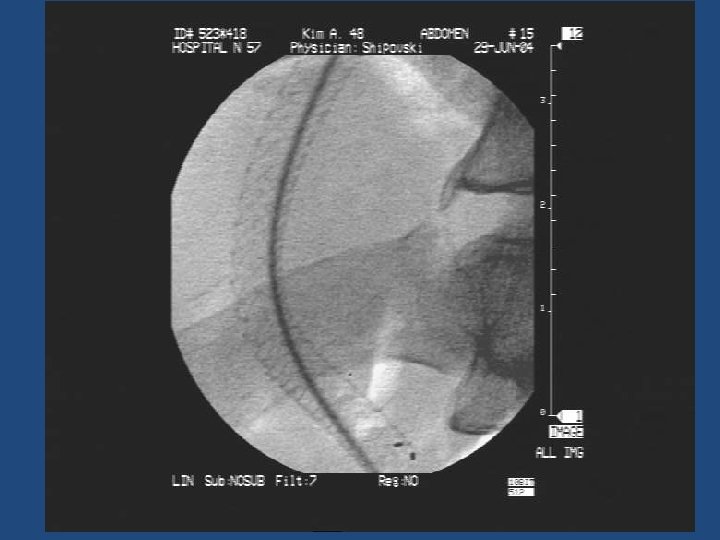

Результаты TIPS • • • Длительность процедуры 1 час до 3, 5 часов Повторные кровотечения – 10% Стеноз стента в течение двух лет – 20% Печеночная энцефалопатия Летальность 20% Максимальный срок наблюдения = 5 лет

Методика дистанционного обследования после TIPS • Клинический осмотр и лабораторные анализы • ЭГДС • Ультразвуковое дуплексное исследование портального кровотока • Ангиография ?